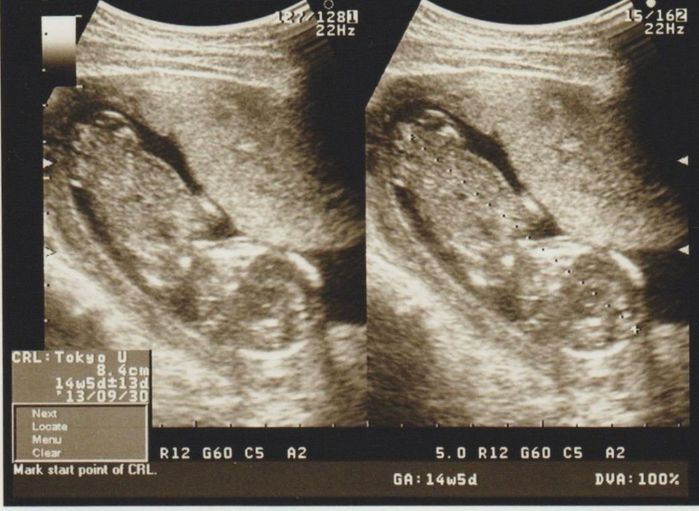

二頭身で確認できる - 妊娠14週目のエコー写真

二頭身で確認できる

写真の右下が頭、左上が足です。人間の形になってきました。先生がエコーで赤ちゃんの足の裏を見せてくれ、思わず「かわいい」と言ってしまった私。そして血液検査の結果、風疹の抗体が少ないことも判明。妊娠中は予防接種を受けることができないため、一番身近のパパに予防接種を受けてもらうよう先生に勧められ、パパが予防接種を受けました。このことが分かってから人混みはできるだけ控えるように気をつけました。